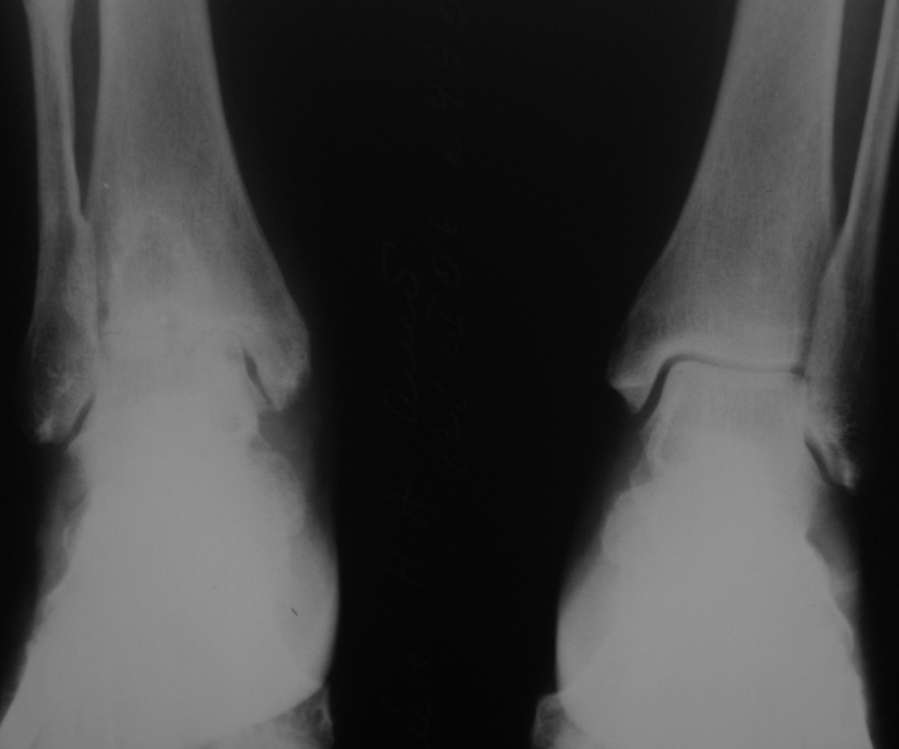

Уважаемые коллеги, разъясните ситуацию.Пациентка, 45лет. 9 месяцев назад произведен синтездвухлодыжечного перелома правой голени.

Конструкции на данный момент удалены. Объем движений на фото. Сейчас беспокоят скованость в области сустава, боли к концу рабочего дня - классическая клиника артроза.Пропила 4 курса найз. Откуда артроз такой выраженности (на рентгенограмме)? Поможет ли консервативное лечение и какое поможет наверняка?

Считаете ли Вы, что объем движений близкий здоровому суставу обеспечивается только подтаранным суставом?

> Считаете ли Вы, что объем движений близкий здоровому суставу обеспечивается только подтаранным суставом?

Нет, подтаранный сустав в основном обеспечивает движения стопы во фронтальной плоскости. Ограничение движений в г\ст суставе компенсируется движениями в среднем отделе стопы

Подтаранный в сгибании/разгибании не участвует вообще. Есть суставы Шопара, Лисфранка. Да и вообще, приемлемость артродеза голеностопного сустава давно обсуждена, что теряется/приобретается - известно, читайте журнал "Здоровье" ;-)